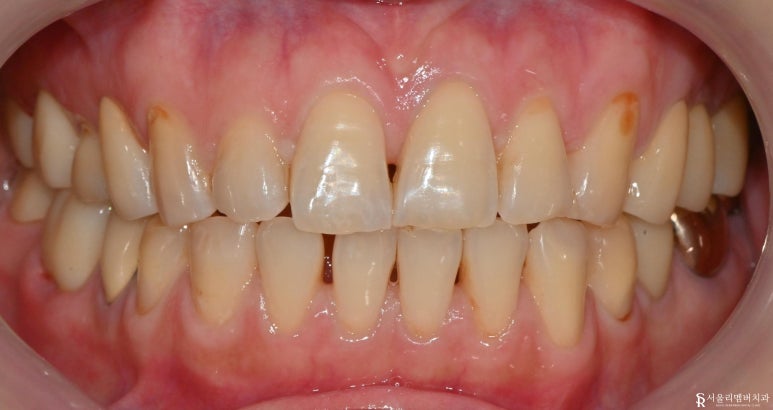

이전과 비교해 보면

앞니 충치들을 모두 제거하고 깔끔하게

심미 레진 치료된 것이 보입니다.

검게 보이던 충치들이 싹 사라졌어요.

신림역 치과 모든 치료를 마치며

치료전 진단 사진과

비교하면 너무 깔끔해 보이는

치료 후 사진입니다.

6개월마다 검진하시는 것을

권장드립니다.